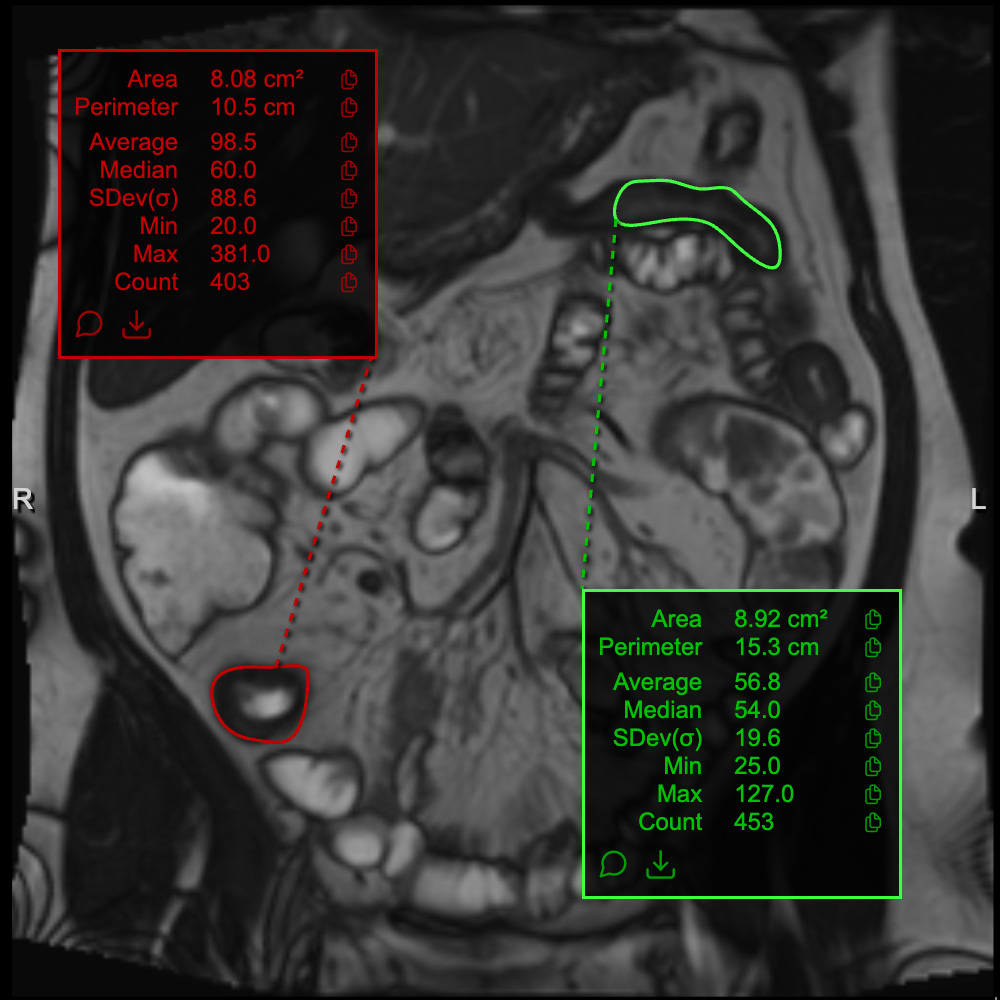

Small bowel strictures in Crohn's disease: a quantitative investigation of intestinal motility using MR enterography

A static stricture and pre-stricture dilation with reduced motility

A static stricture but some activity pre-dilation

A lively stricture with some contractions in the stricture and vigorous peristalsis upstream